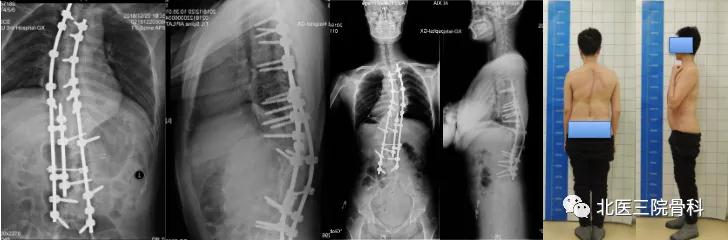

病例二

先天性脊柱侧后凸畸形大体照及影像学

(术前)

(术后)